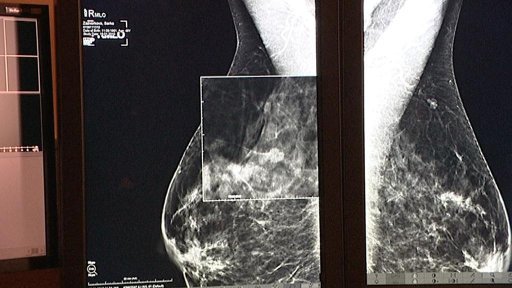

Headlines — První pokuty za chyby v projektech Regionálního operačního programu Severozápad — Další vlna pokut přinese ROP Severozápad stamiliony — Naděje pro Velichovky — Na Vysočině teď chybí sociálním zařízením zhruba 24 milionů korun — Výstava mamografických snímků v Českých Budějovicích — Srážka vlaku s kamionem na přejezdu v Brandýse nad Labem — Pražští radní schválili stavbu metra D — Lidem v Želízech jezdí kamiony pod okny — Kamerový systém, nebo asistent prevence kriminality? — Poslední budova liberecké Textilany chátrá — Volební debata — Vodohospodáři ve Frýdlantu řeší, jak zajistit dodávky pitné vody pro celé město — Filmové město přišlo o jediné velké kino — Plyšový maraton nadělil hračky dětem z azylových domů — Pražský Petřín bude přírodní památkou — Speciální zdravotní stezka v Ústí nad Labem